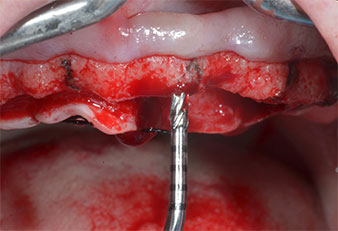

Un insert piézoélectrique diamanté de forme effilée (Piezomed I1) a été utilisé pour marquer les positions implantaires et effectuer la préparation pilote (Fig. 3). On a pris soin de travailler selon un mouvement ascendant et descendant, à puissance réduite, irrigation complète et basse pression (moins de 300g). Ensuite, un insert pilote (Piezomed I2A/I2P) a été utilisé pour l’agrandissement initial de 2mm du diamètre des sites implantaires (Fig. 4), suivi d’un insert de 3mm (Fig. 5).

Insert marqueur à ultrasons Piezomed

Fig. 3 : L’insert marqueur à ultrasons Piezomed I1 sert à effectuer la préparation selon un mouvement ascendant et descendant, parallèlement à l’axe le plus long de la partie active.